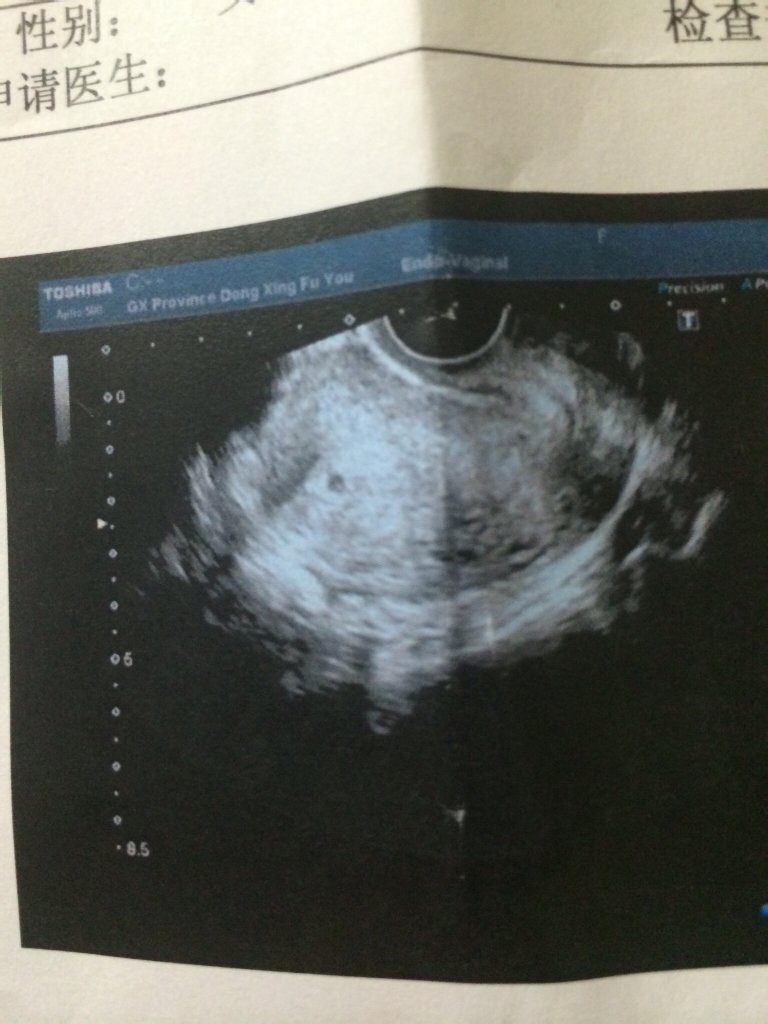

今天去检查了,医生说有可能是双胞胎,因为还很小,所以麻烦你们帮看看,这样算是双胞胎吗